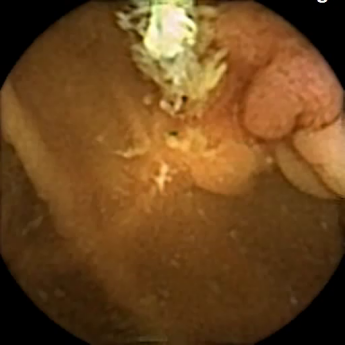

(b) I: None -

R: Polyp

Figure 5: Representative VCE images, that were identified as mislabeled by our pipeline and re-annotated by clinical experts (I: Initial, R: Revised).

Furthermore, Figure 5 displays four representative VCE images identified by our proposed approach as mislabeled data, which were subsequently confirmed as incorrectly labeled by the scientific panel and re-annotated accordingly. The first two images were originally annotated as healthy mucosa, but have been corrected to angiectasia (Figure 5a) and polyp (Figure 5b). The second two frames were originally labeled as blood (Figure 5c) and polyp (Figure 5d), but were identified as normal samples by our pipeline and then relabeled respectively. This indicates the effectiveness of our pipeline in detecting present mislabeled data in medical datasets.